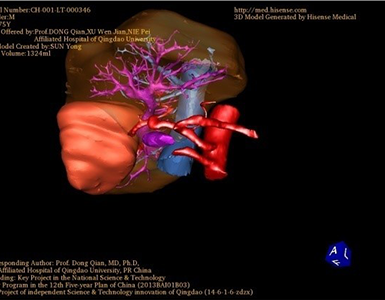

胆管细胞癌-CH-001-LT-000346

一般情况:CH-001-LT-000346,74岁男性患者。

将0.625mm双源薄层CT资料的静脉期和动脉期Dicom格式文件导入海信CAS系统。

通过调节窗宽窗位调整CT序号,对肿瘤,肝实质,胆囊,下腔静脉,肿瘤,肝动脉、门静脉及肝静脉等进行三维重建;系统自动计算肿瘤体积和肝脏体积。(图2—截图1---后链接截图2)

模拟手术操作,自动计算切除肿瘤体积。肝脏体积为1324ml,肿瘤体积为286.1ml,肿瘤体积为肝脏体积的21.6%,通过比对70-80岁正常肝脏体积为1118.08±190.14ml,通过术前模拟手术,精准判断切除后剩余肝脏体积能耐受,避免肝衰竭发生。术前手术方案的规划。

术前三维重建:

重建图片